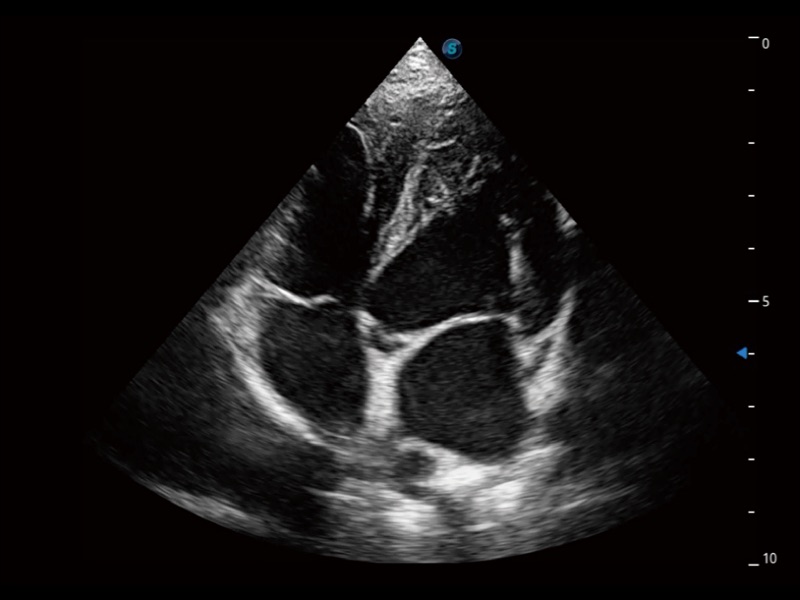

能够基于左心室壁追踪和辛普森法,自动计算射血分数,支持多个可移动点描迹,与手动测量相比,极大节省了动物医生的时间和精力。

通过360度任意调节3条M型取样线,在同一心动周期上观察心脏不同位置的运动曲线,得到准确的心功能测量数据,有效评估心肌运动及左心室功能。

实时用颜色表示心肌组织运动,观察和定量组织的运动情况,对快速检测与评估心肌的灌注和活性、电传导及心肌收缩和舒张功能等均能提供重要的诊断信息。